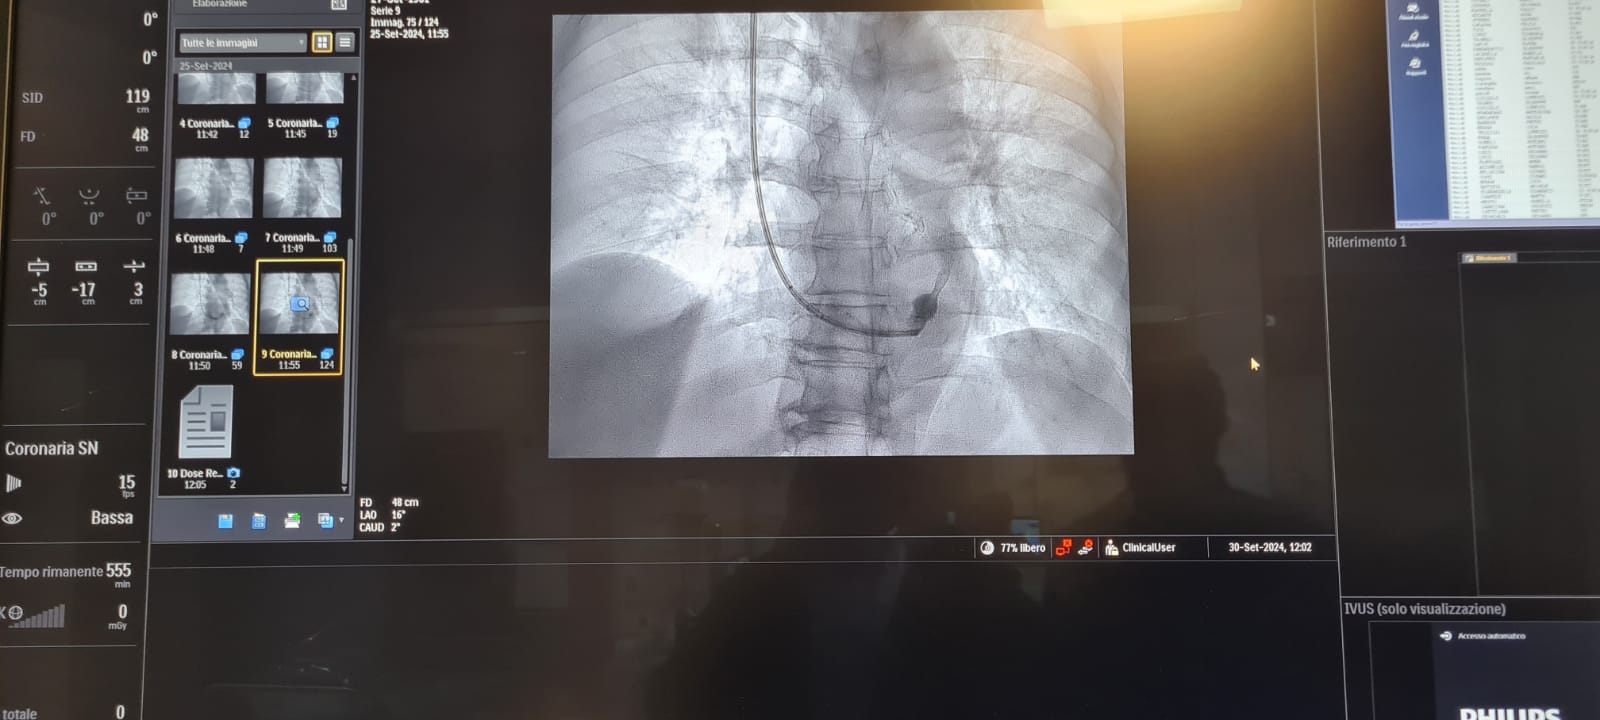

«Abbiamo eseguito questo intervento invasivo ma non chirurgico - ha spiegato Bonfantino - in un paziente di 63 anni, in anestesia locale, che è consistito nell’impianto di uno stent metallico, a forma di clessidra, attraverso la vena giugulare, all’interno del seno coronarico, cioè la vena che sbocca nell’atrio destro del cuore e che drena tutto il sangue venoso di origine cardiaca, per poi raggiungere i polmoni ed essere ossigenato».

L’impianto dello stent in sala è stato coordinato dal dottor Maurizio Turturo, responsabile della unità Emodinamica, e dal dottor Francesco Cassano. «Grazie alla particolare morfologia dello stent, a forma di clessidra - ha detto Turturo - si determina un rallentamento del drenaggio venoso cardiaco, permettendo la persistenza nel cuore di sangue ancora ossigenato e quindi il rilascio di una maggiore quantità di ossigeno al muscolo cardiaco».